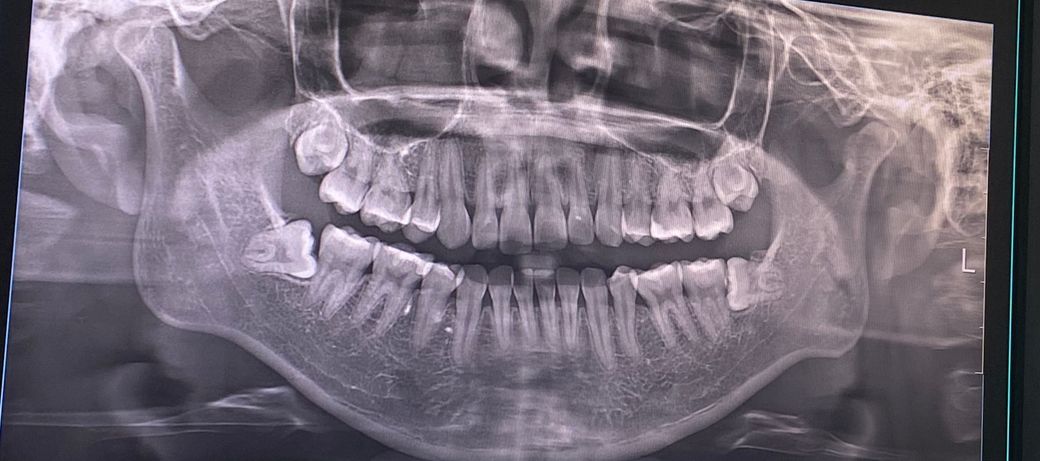

곧 사랑니 발치를 앞두고 있는데요, 너무 무섭고 긴장되서 여쭤봅니다😢 동네 대학병원에 매복치아 발치 전문으로 하시는 교수님 예약해두었구요. 교수님께서는 마취주사부터 봉합까지 30~45분 걸린다는데… 이정도면 많이 어려운 난이도인가요??ㅠㅠ

아래 사랑니는 옆으로 누워있는 수평매복 사랑니 입니다. 이런 사랑니는 치아를 부수는 치아절단술로 발치해야 하니 수술에 해당하며 외과적 발치술이라고 합니다.

사진상으로 보면 크게 어려운 난이도는 아닌거 같습니다. 더군다가 대학병원 교수님이라면 30분정도 걸리실꺼 같네요.

크게 복잡한 수술은 아닌 것으로 보입니다. 시간은 말씀하신 대로 30분~1시간까지 걸릴 수 있어 보입니다.

사랑니가 완전 매복 상태가 아니며 앞에 치아나 하악 신경과도 거리가 있어서 크게 문제가 있을 것 같지는 않습니다

대학병원에서 교수님 진료 받으신다면 크게 걱정 안하셔도 괜찮습니다